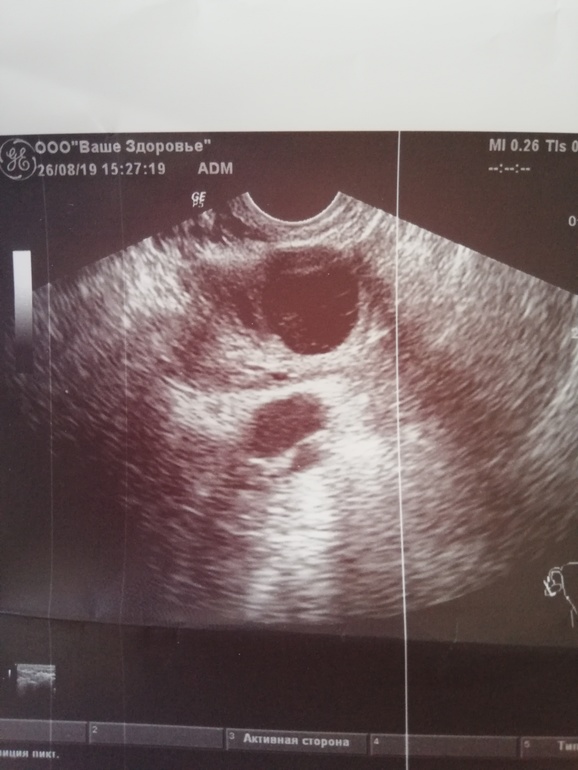

Здравствуйте девочки прошу помощи, вообщем на 14дмц,была на узи сказали что есть желтое тело 17мм, сейчас 22дмц пришла на узи сначала врач сказал что жт16 мм, рядом киста 17мм, а потом нет, мол это все кистозное желтое тело 30мм, 3 цикл отмены кок, в 1 месяце отмены была киста фолликулярная, в том месяце все чисто было, и вот сейчас вот так. Может быть переделать узи? Или что нибудь посоветуйте пожалуйста